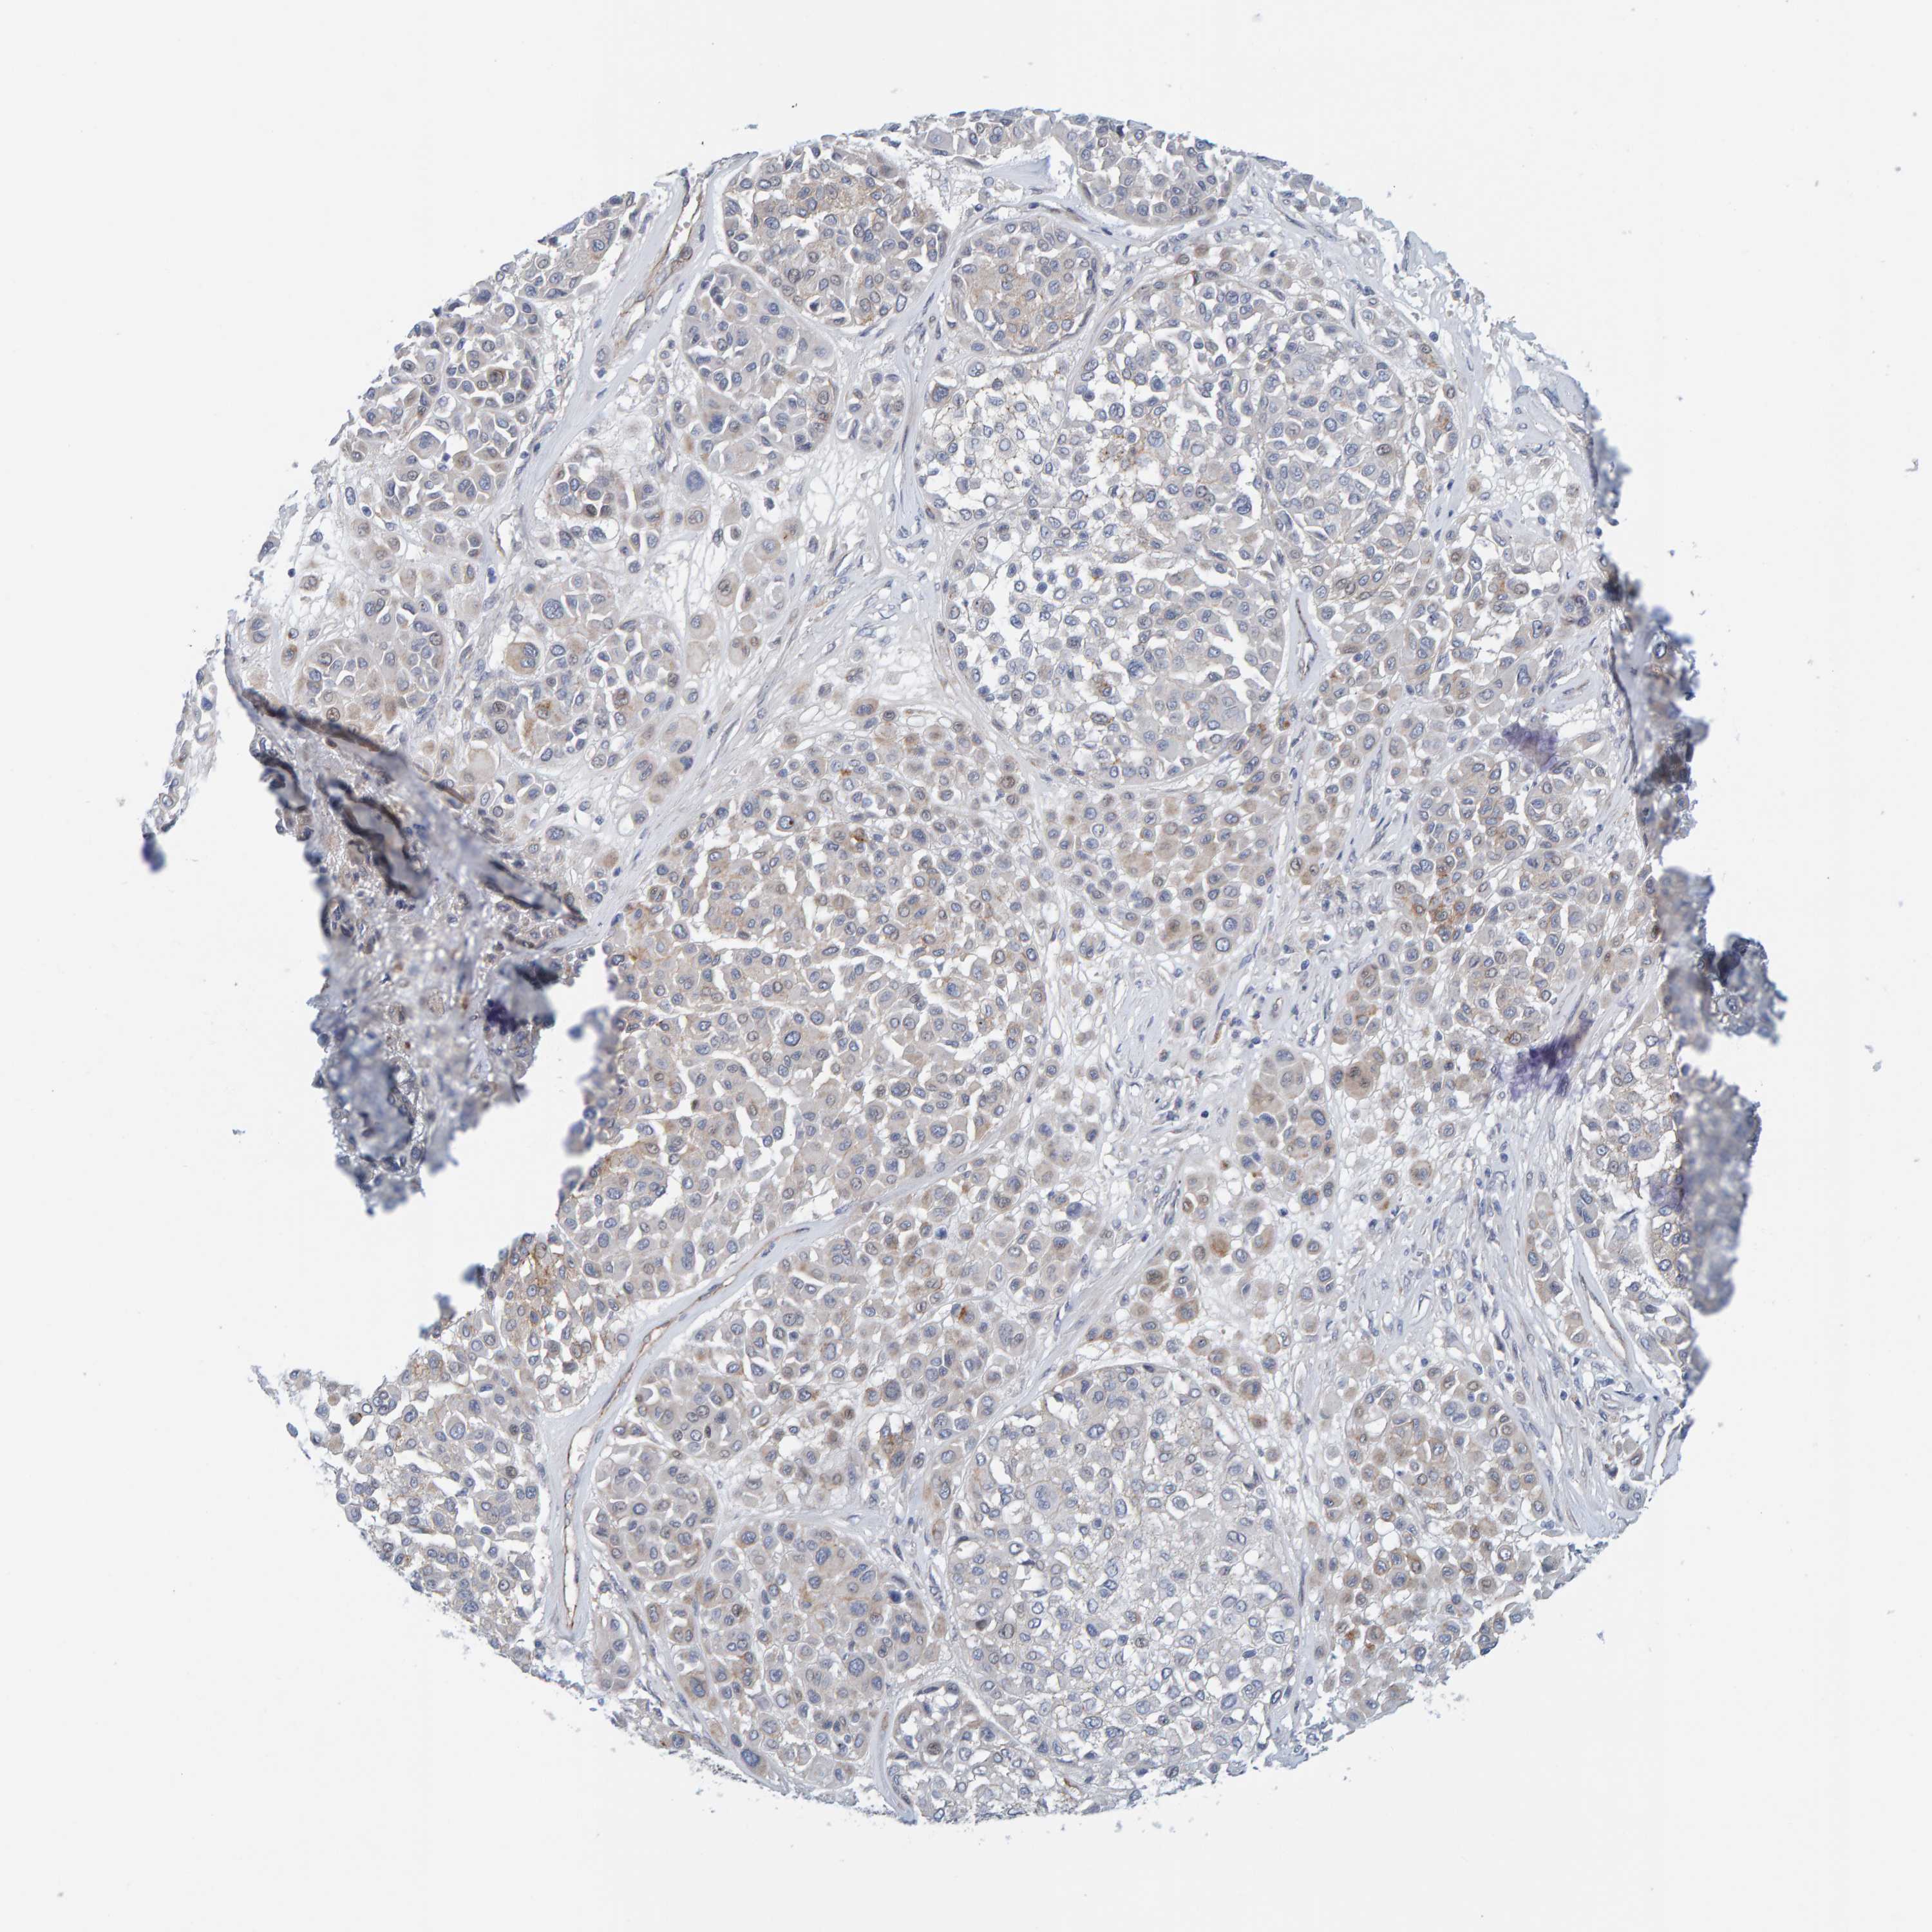

MELANOMA - Protein expressioni

A mouse-over function shows sample information and annotation data. Click on an image to view it in a full screen mode. Samples can be filtered based on level of antibody staining by selecting one or several of the following categories: high, medium, low and not detected. The assay and annotation is described here.

Note that samples used for immunohistochemistry by the Human Protein Atlas do not correspond to samples in the TCGA dataset.

Antibody stainingi

Antibody staining in the annotated cell types in the current human tissue is reported as not detected, low, medium, or high, based on conventional immunohistochemistry profiling in selected tissues. This score is based on the combination of the staining intensity and fraction of stained cells.

Each image is clickable and will lead to virtual microscopy that enables deeper exploration of all samples and also displays staining intensity scores, fraction scores and subcellular localization as well as patient and tissue information for each sample.

Antibody HPA022849

Staining

High

Medium

Low

Not detected

Intensity

Strong

Moderate

Weak

Negative

Quantity

>75%

75%-25%

<25%

None

Location

Nuclear

Cytoplasmic/membranous

Cytoplasmic/membranous,nuclear

Malignant melanoma, NOS

Malignant melanoma, Metastatic site